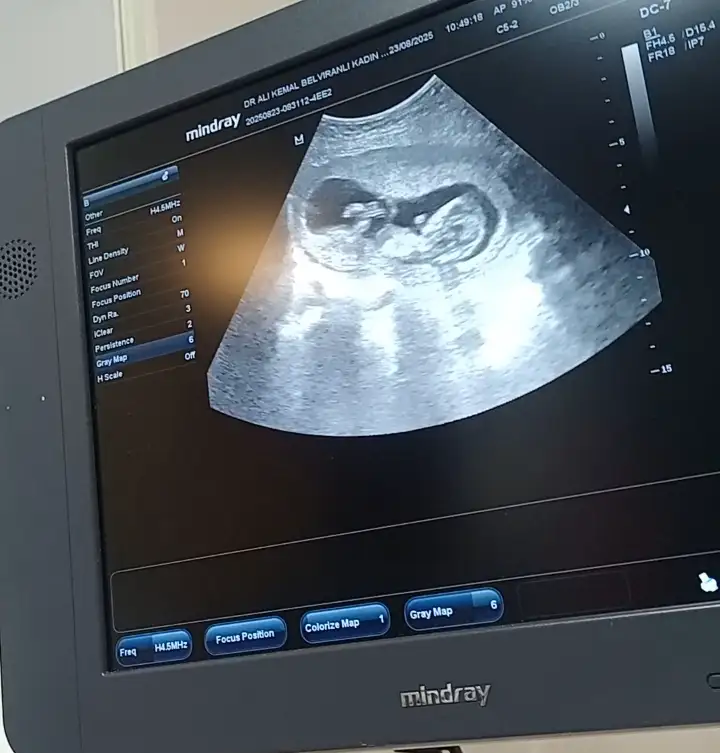

Merhaba yeni görüntüler var sizce ne olabilir doktorum bir tahminde bulundu ama sizin fikrinizi merak ediyorum

13+4 tahminde bulunabilir misiniz şimdiden teşekkür ederim.